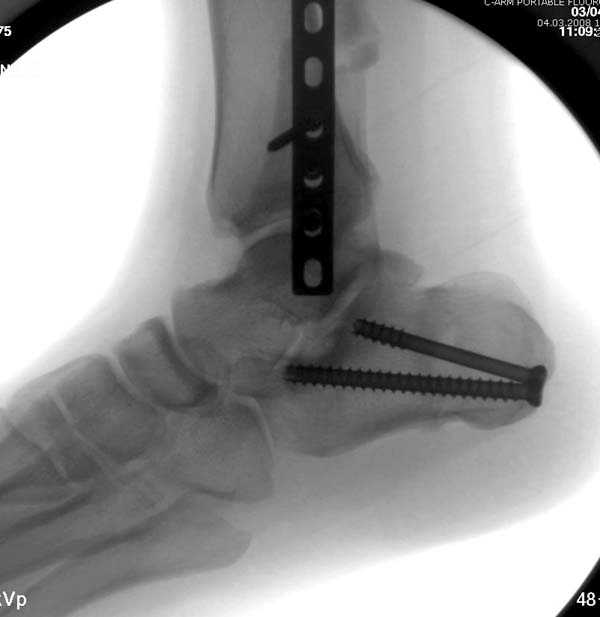

Здесь представлено решение похожей проблемы. Больной в течение года лечился консервативными мерами, и боли в голеностопе были основным показанием к операции.

Проведена обычная стандартная процедура по исправлению неудовлетворительного состояния голеностопного сустава, где кроме удлинения малоберцовой с применением compression tension device за проксимальный конец пластины, проведено замещение трикортикальным графтом из крыла, освобождение синдесмоза и медиальной щели от

фибротических масс с фиксацией.

Дополнительно у больного плоская стопа, во время операции провели небольшую скользящую остеотомию, надеемся, что поможет.